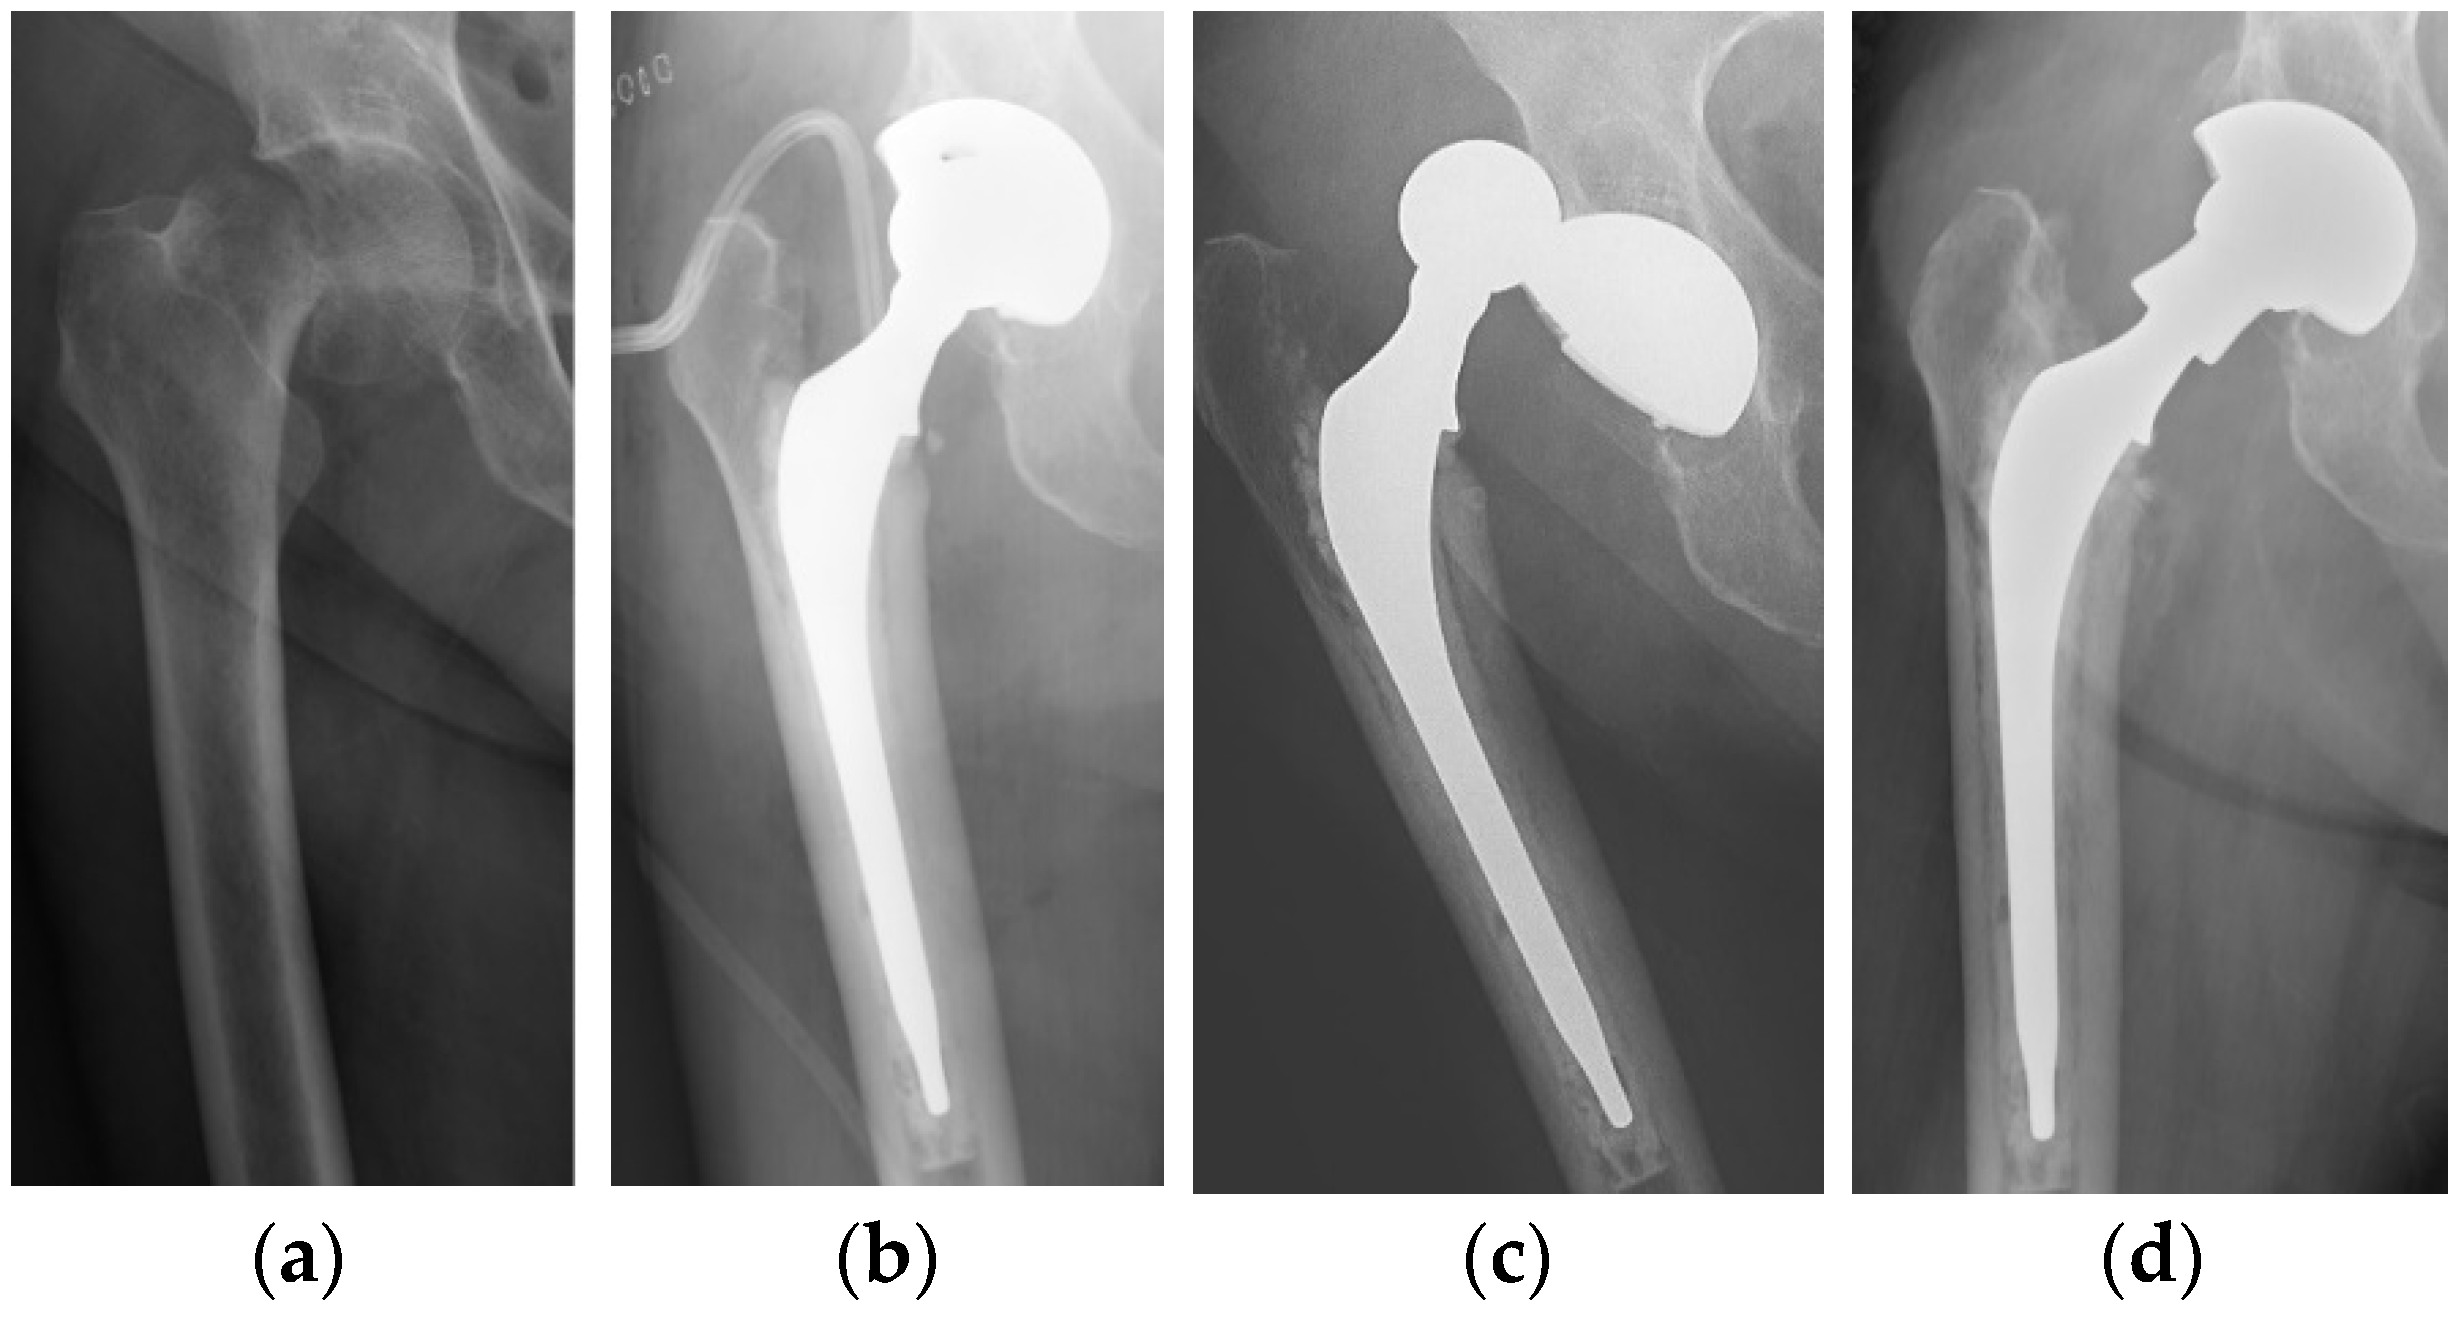

Radiographic signs of acetabular osteointegration at 1 year (Figure 2) were found in 42 patients (87.5%): 20 in the DMC group (83.3%) and 22 in the SC group (91.6%), with a non-significant difference (p-value = 0.98). No cases of implant mobilization were detected on X-rays. Heterotopic ossifications had a similar incidence in the two groups: four in the DMC group and three in the SC group (p-value = 0.99).

Figure 2. (a) Postoperative radiograph of a DMC showing (arrows) a radiolucent line at the bone-implant interface. (b) Radiographic evidence of implant osteointegration one year after surgery.

Radiographic examination did not reveal any complication at 1-year follow up, with a rate of 87.5% (42/48) osteointegrated cups in the total population. The SC group showed a higher number of osteointergrated cups than DMC (22 vs. 20), but this difference was not significant. It must be noted that the DMCs used in our series did not allow for the insertion of screws to increase primary stability of the acetabular cup. This is a drawback in patients with compromised bone quality and might require cement fixation. In a recent study, Sunilkumar et al. highlighted the risk of improper cup fixation and periprosthetic acetabular fractures with the use of DMCs for FNF in elderly patients [49]. The lack of screws for fixation and the inability to visualize the acetabular floor during impaction were considered disadvantages of this implant, particularly in presence of osteoporotic bones.